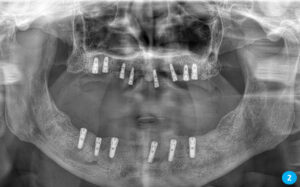

İlk aşamada implant çene kemiğine yerleştirilir. Ardından ortalama 3 ay kadar kişiden kişiye değişiklik gösteren bekleme süreci olur. Bekleme sürecinin amacı kemik oluşumu ve implantın çene kemiğine kaynaşmasını sağlamaktır. Bu süreç bittikten sonra implantın üst yapısının yapılması ise 1-2 haftalık bir zamanda bitmektedir.

Alt-üst damakta hiç dişi olmayan hastalar hareketli proteze alışamamakta, bulantı reflefsi oluşturmakta ve çoğu hastada damaklar ağızda sıkı bir şekilde durmamaktadır. Bu durum hastaları sosyal yönden olumsuz etkilyebilmektedir. Hiç dişi olmayan hastalara implant önemli bir çözüm oluşturmaktadır.